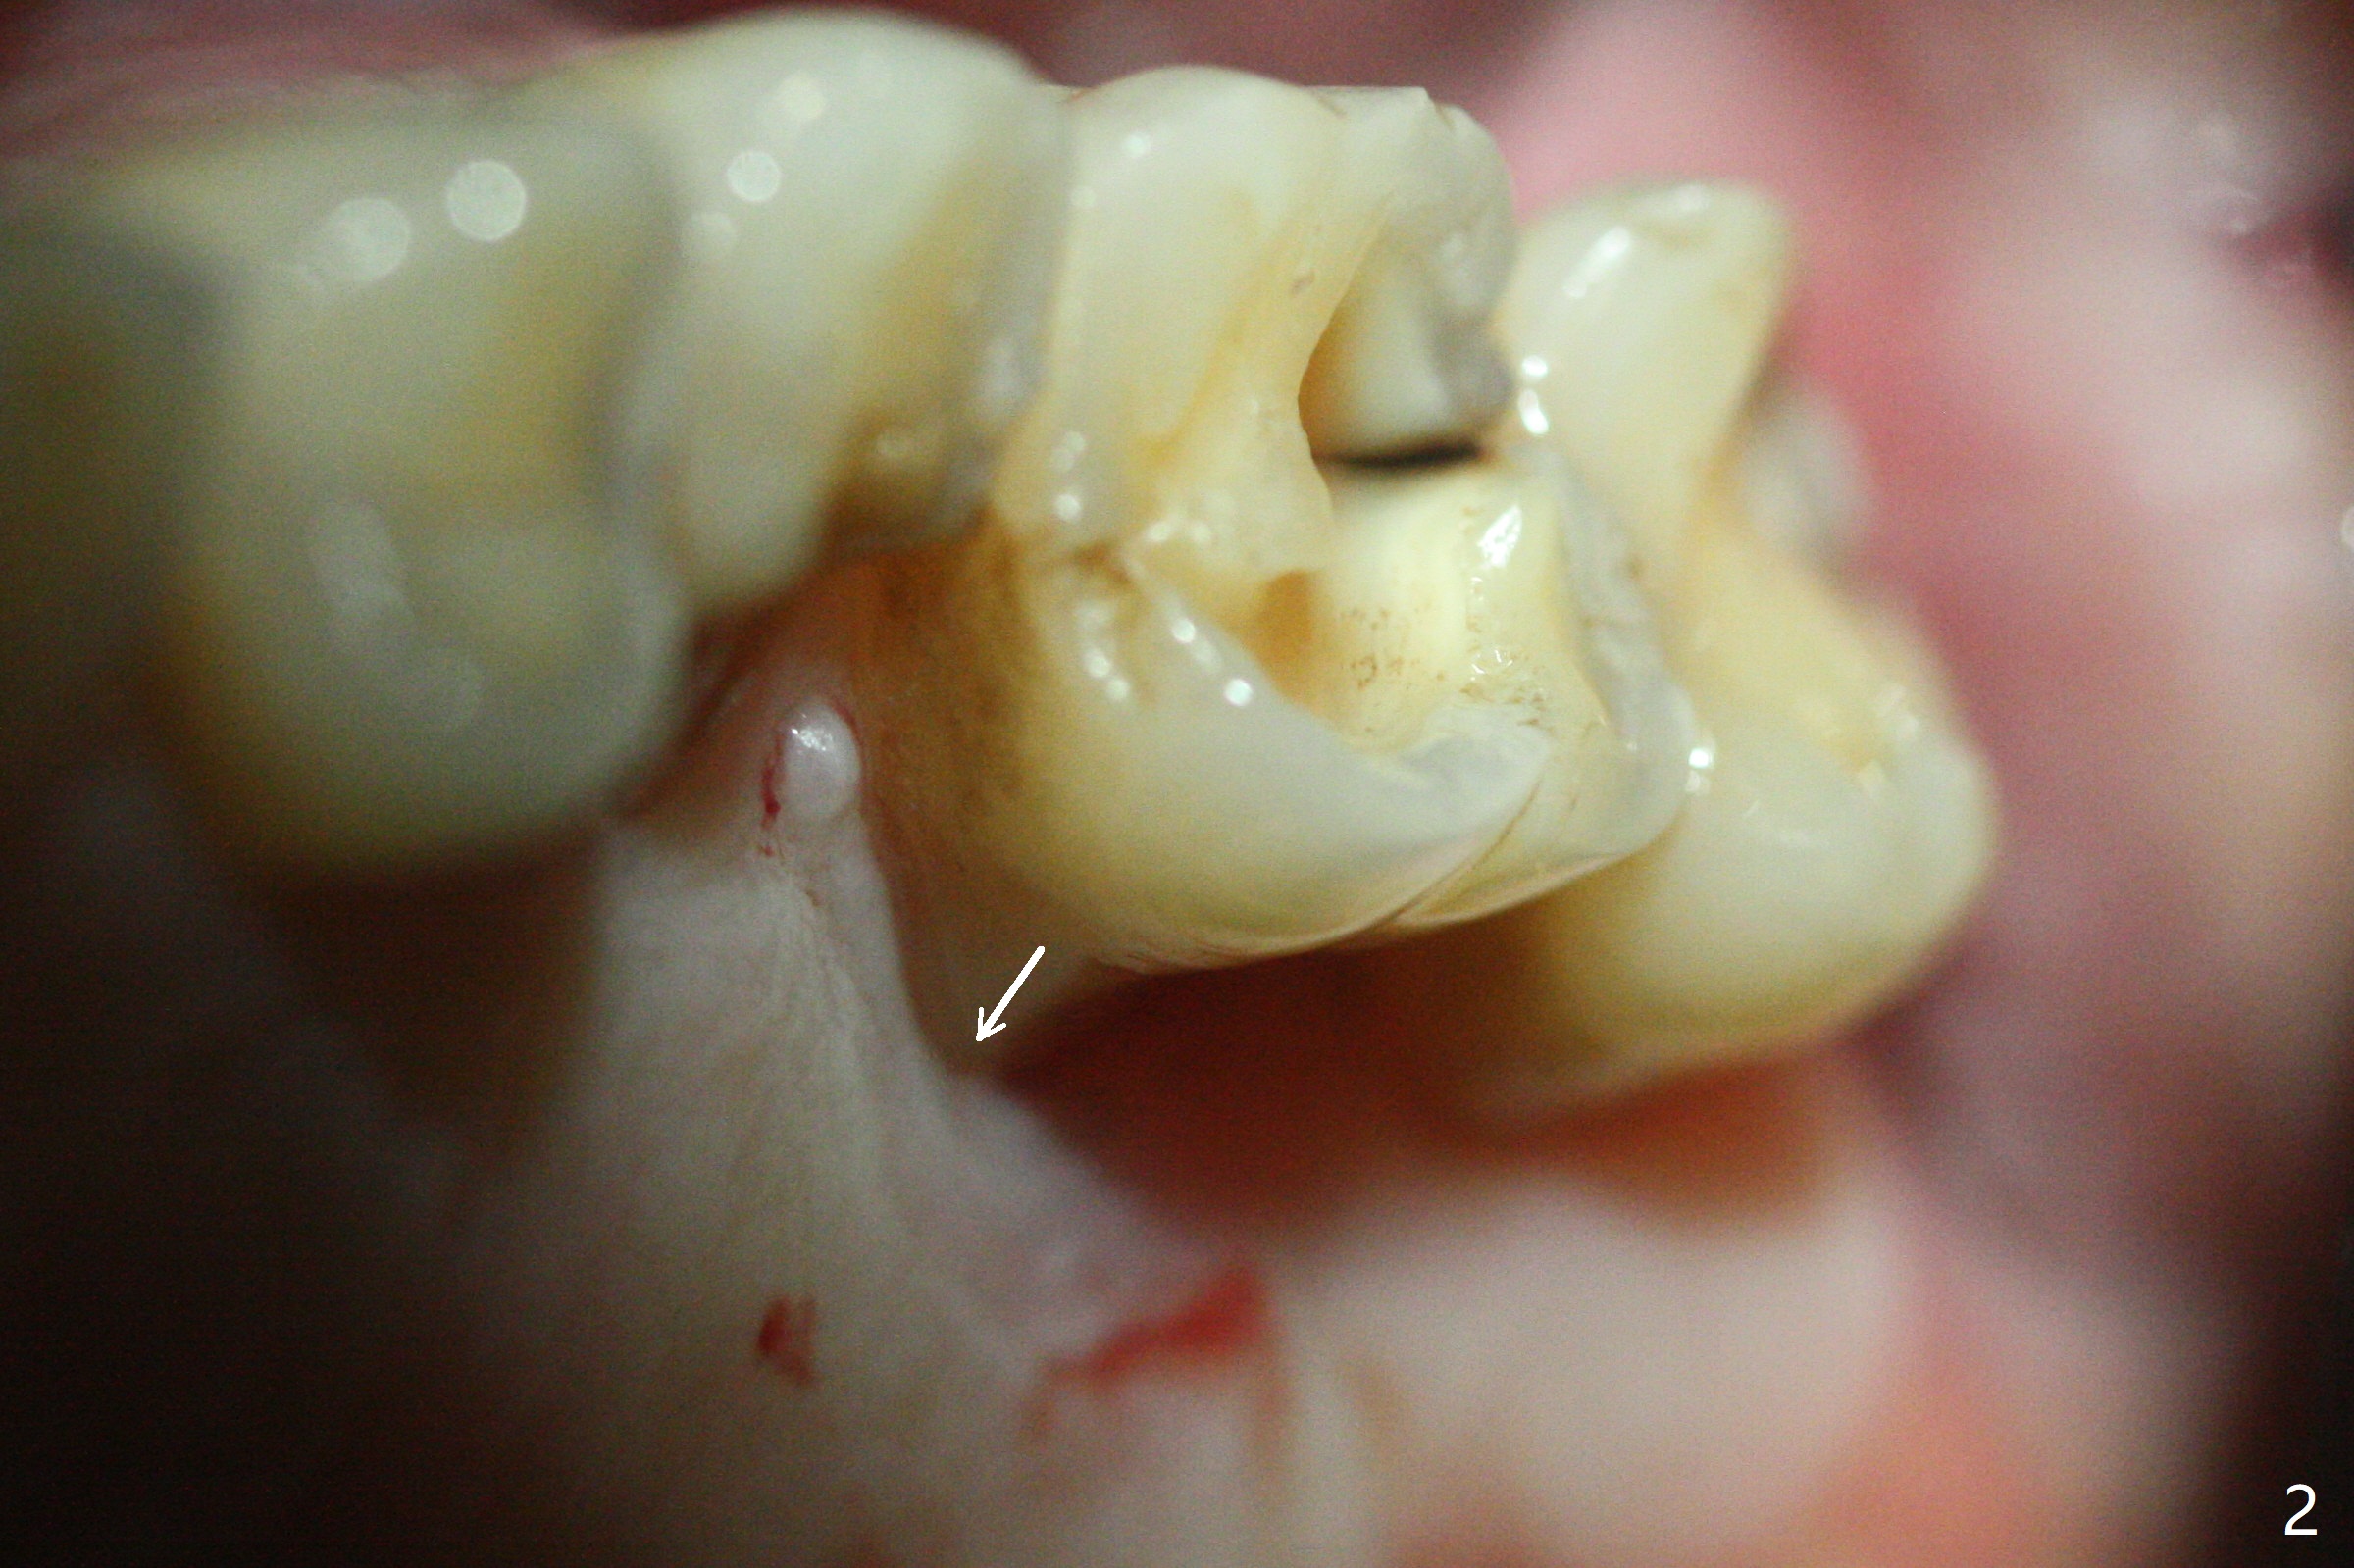

尽管14号牙远中裂纹(图一:箭头),冷热痛,拔除时腭侧根表面覆盖结石,似乎没有牙周膜附着。虽然牙龈萎缩不明显(图二:箭头),拔除后检查显示腭侧骨板缺失一直到根尖。使用10.5 和12毫米bone trimmers后中隔平面偏向近中,使用设计最后一个钻头(3x10mm)后,钻洞已经进入近中颊侧牙槽窝,由于植入4x9毫米植体扭力高于35 Ncm,使用3.5x7.3,3.5x8.5毫米钻头(也可以减少植体腭侧偏移)后,扭力20Ncm(图三),腭侧一个螺纹暴露。放置基台后,填入粘性骨粉(*),远中颊侧牙槽窝可能与腭侧牙槽窝重叠。制作临时牙冠,衬里,取出牙冠,覆盖PRF后,盖上牙冠,检查牙冠与对合牙分开~1毫米。术后一周临时牙冠与腭侧牙龈接触紧密,覆盖巨大腭侧缺损。如果没有临时牙冠,关闭腭侧缺损谅必困难,可能出现骨粉暴露。